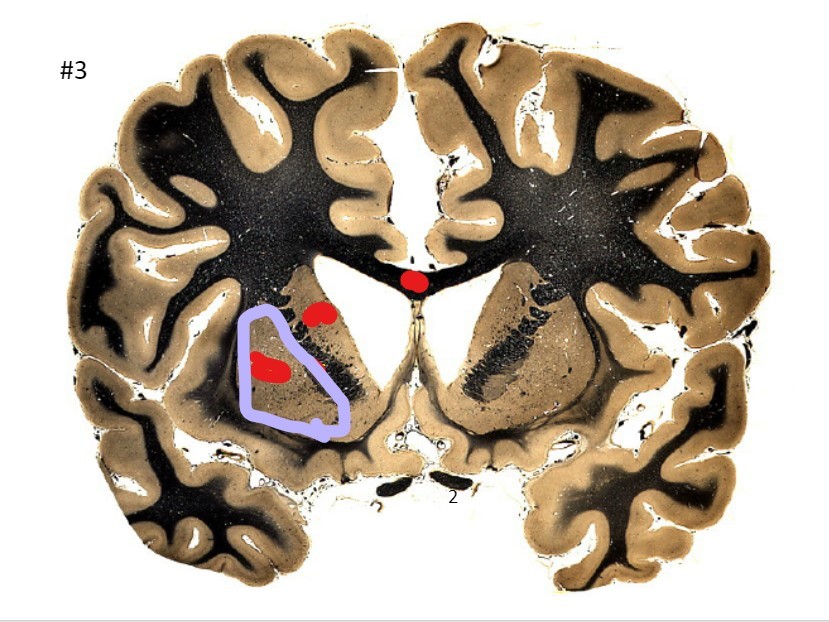

what is the circled area (#3)?

A

the corpus callosum

Q

the caudate nucleus

7

the internal capsule

8

the putamen

9

the optic nerve